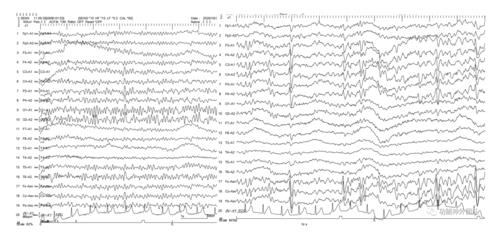

痫样脑电图,有癫波的脑电图图

睡眠中患者长程视频脑电图

动态脑电图可见额叶和颞叶阵发性尖慢波和棘波.

术后4个月复查脑电图提示睡眠期见左前头部缺损节律,未见异常放电.